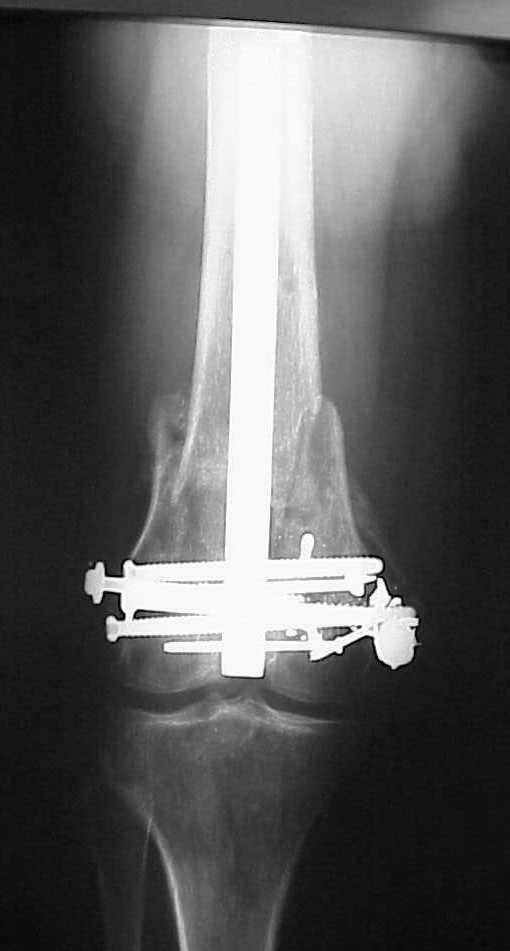

Use 6.5 mm cannulated screws if you have and

place one anterior to where IMN will go if anterior cortex if insufficient and AP screws on either side of the IMN out of the trochlea to provide some additional varus/valgus stability. I worry about the leg going into valgus w/the lack of lateral cortex.

See attached case that was done several years ago before LISS. He had comminuted trochlea and anterior blocking screws were used to prevent anterior IMN cut-out.